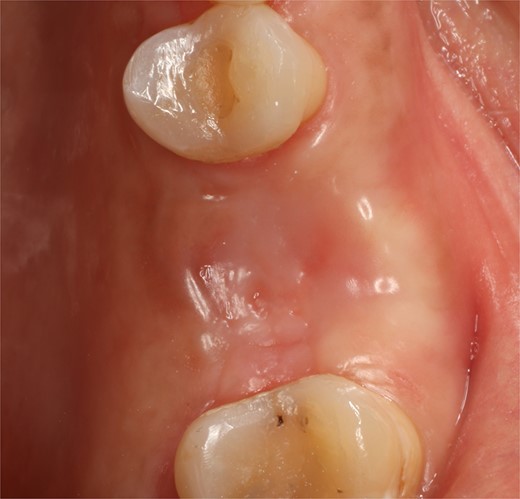

A 56-year-old female patient without any systemic diseases was referred by otolaryngology for evaluation by oral surgery due to presenting pain on the left side of the face for two weeks. The patient’s first molar presented a wide restoration (Fig. 1). This molar had undergone endodontic treatment some years ago. The CT scan showed a hyperdense left maxillary sinus almost entirely with loss of continuity of the maxillary sinus floor at the level of the left upper first molar involving the furcation zone, it is evident an oroantral communication of 7 mm (Fig. 2). The patient referred to spontaneous pain during chewing. Based on the CT scan and the clinical findings, pharmacological management was indicated with oral antihistamine 10 mg every 24 hours for 10 days, Moxifloxacin 400 mg every 24 hours, and scheduled extraction with oroantral communication closure with collagen sponge on the third day after starting the antibiotic, which will be used for a total of 10 days. The patient agreed to sign an informed consent file to make the technique to extraction and close the oroantral communication.